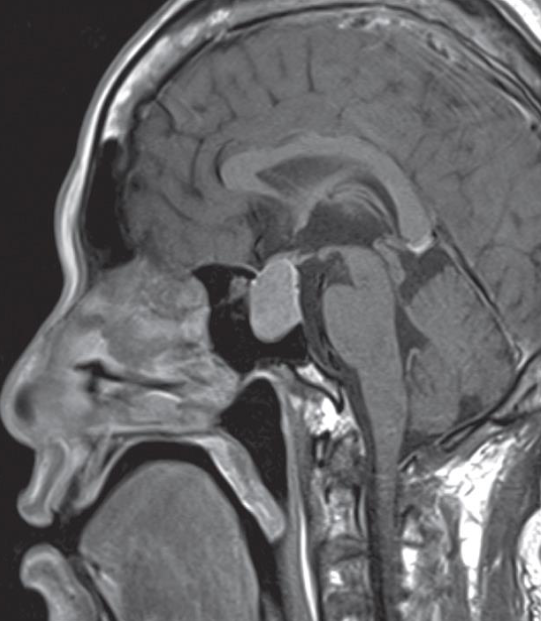

Agenesis of corpus callosum

Sagittal T1 MRI brain